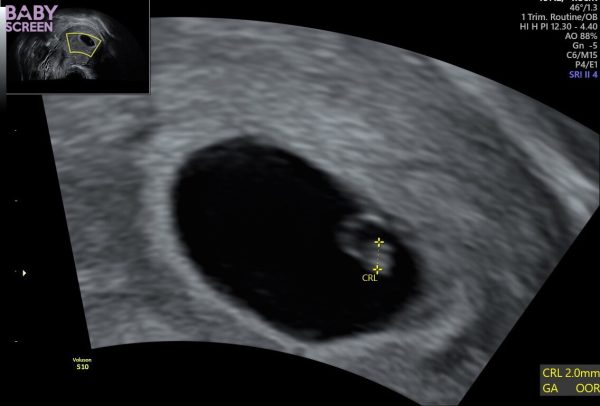

Idag följde jag Ida på ett första tidigt ultraljud som visar att hon precis gått in i vecka 7 av hennes graviditet. Ett litet hjärtslag syntes också ❤️